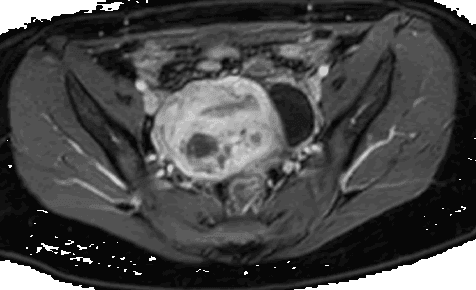

सबम्यूकस सिस्टिक एडिनोमायोसिस, महिलाओं में एक आम गर्भाशय सम्बन्धी रोग है जिसमें गर्भाशय के भीतर एडिनोमायोसिस नामक अव्यवस्था होती है। इस रोग के कारण महिलाओं को अनियमित मासिक धर्म, गर्भाशय के क्षेत्र में दर्द और प्रभावित स्तन की समस्याएं हो सकती हैं। हालांकि, अधिकांश मामलों में यह समस्या बेहद सामान्य और गंभीर नहीं होती है।

सबम्यूकस सिस्टिक एडिनोमायोसिस के प्रबंधन के लिए, हिस्टेरोस्कोपिक प्रक्रिया एक महत्वपूर्ण विकल्प है। हिस्टेरोस्कोपी एक चिकित्सा प्रक्रिया है जिसमें एक विशेष यंत्र का उपयोग करके गर्भाशय को देखा जाता है। इस प्रक्रिया में, एक छोटी सी ट्यूब को गर्भाशय के माध्यम से डाला जाता है, जिसमें एक कैमरा लगा होता है। यह कैमरा दर्शक को तस्वीरें दिखाता है और चिकित्सक को सबम्यूकस सिस्टिक एडिनोमायोसिस के लिए सही इलाज की योजना बनाने में मदद करता है।